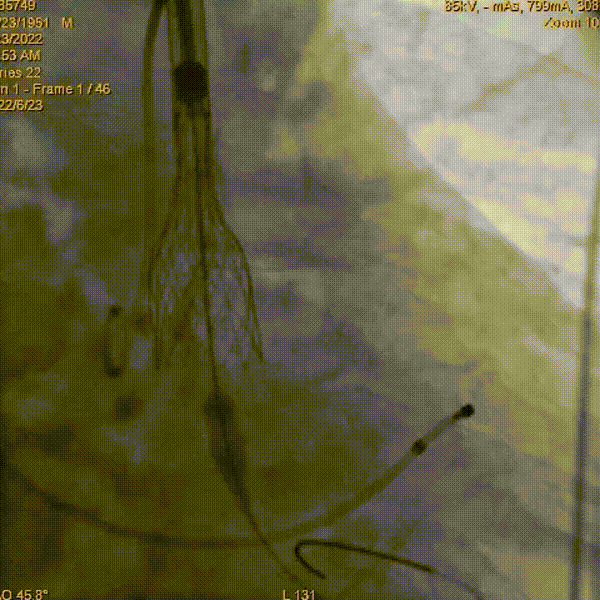

AV26mm瓣膜完全释放

术后主动脉根部造影

位置良好,无瓣周漏